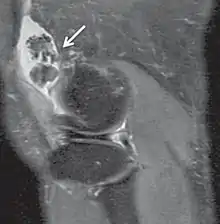

| Proton density weighted | PD | Long TR (to reduce T1) and short TE (to minimize T2).[7] | Joint disease and injury.[8]

Proton density (PD)- weighted images are created by having a long repetition time (TR) and a short echo time (TE).[36] On images of the brain, this sequence has a more pronounced distinction between gray matter (bright) and white matter (darker gray), but with little contrast between brain and CSF.[36] It is very useful for the detection of joint disease and injury.[37]